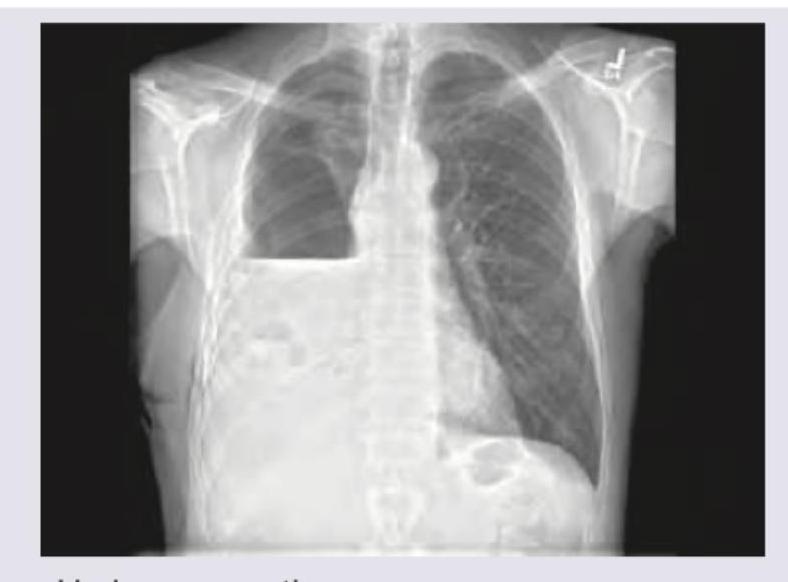

Explanation: ***Pneumothorax*** - A **pneumothorax** is characterized by the presence of **air in the pleural space**, which typically appears as a **lucent area** without lung markings and a displaced visceral pleural line on X-ray. - The presented chest X-ray shows **dense opacities at the lung bases**, consistent with fluid accumulation (**pleural effusion**), not air. *Left-sided pleural effusion* - The image clearly shows significant **opacification of the left hemithorax** with blunting of the **costophrenic angle** and obscuring of the left hemidiaphragm. - This finding is consistent with a large amount of fluid, indicating a **left-sided pleural effusion**. *Mediastinum shifted to right* - The **trachea** and **cardiac silhouette** are visibly displaced towards the **right side** of the chest. - This shift is a consequence of the large **left-sided pleural effusion exerting mass effect** and pushing the mediastinal structures away from the affected side. *Bilateral ICD tubes* - There are discernable radiopaque lines extending into both pleural spaces, representing **bilateral intercostal drainage (ICD) tubes**. - These tubes are placed to drain the **accumulated pleural fluid** from both the right and left sides.